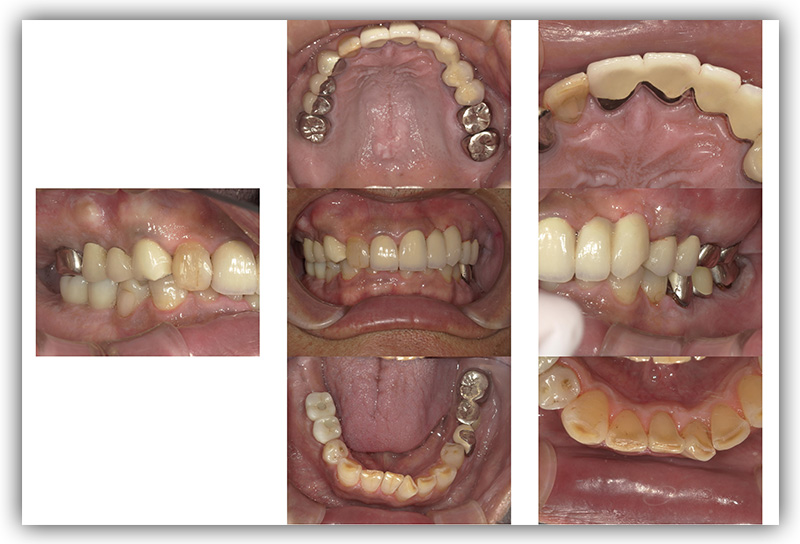

CASE_02

60代男性(インプラント)

- 60代 男性

- 被せものが外れたところをインプラントにしたい

- 2箇所

- インプラント

- 約86万円

- 約半年

- 治療期間がながい、外科的治療が必要